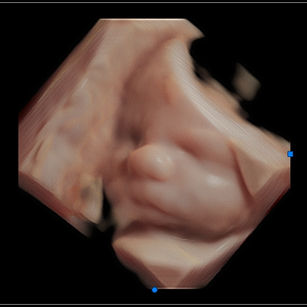

Baby is also practicing grasping, sucking, and even hiccupping.

Muscles: Strengthening—movements are more coordinated and powerful.